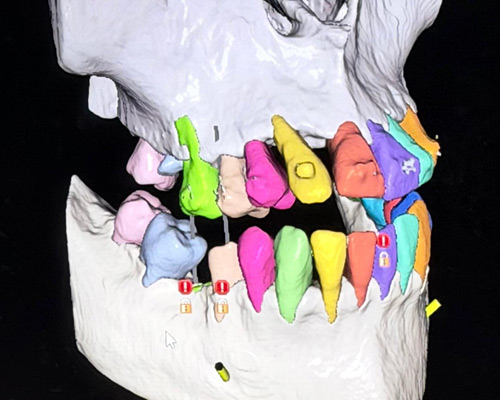

* Dr. Mongalo will review all Ct-scans and 3D images of surgical patients operated on daily.